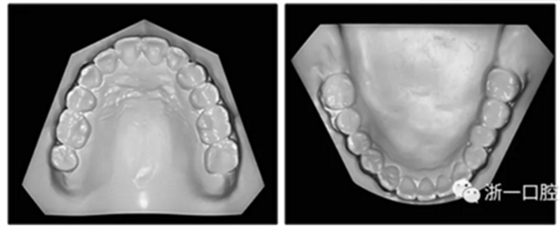

36歲;女性;尋求下頜左后方區(qū)域間隙管理的建議(圖1和圖2),通過(guò)治療獲得了良好的牙頜面效果(圖3和圖4)。她被診斷患有骨性I類和代償性牙性II類錯(cuò)合畸形,并且上頜左側(cè)尖牙缺失(圖1和2)。大約七年前,由于不可修復(fù)的齲齒,拔除了下頜左側(cè)第一和第二磨牙(圖5)。37相鄰的第三磨牙向近中移動(dòng)并傾斜入間隙,導(dǎo)致無(wú)牙頜間隙減小至約14 mm(圖2和圖5)。臨床和影像學(xué)評(píng)估顯示多發(fā)性齲損和在下頜右側(cè)567處有一不良的固定橋修復(fù)體(圖1和5)。此外,下頜左中切牙缺失,造成下頜中線向左側(cè)偏移約3 mm(圖1和圖2)?;颊咦栽V,她的右上第一前磨牙和左上尖牙在13歲時(shí)由其家庭牙醫(yī)拔除,因?yàn)樗鼈儽蛔枞筋a側(cè)萌出(圖1)。上頜第二磨牙缺失(未知病因),并且相鄰的第三磨牙已經(jīng)轉(zhuǎn)移到第二磨牙間隙中。如補(bǔ)充材料所示,美國(guó)正畸學(xué)差異指數(shù)DI是28分。種植體部位(下頜左側(cè)和右側(cè)第一磨牙)由于復(fù)雜性得到額外4分(補(bǔ)充材料)。

圖2. 治療前牙齒模型